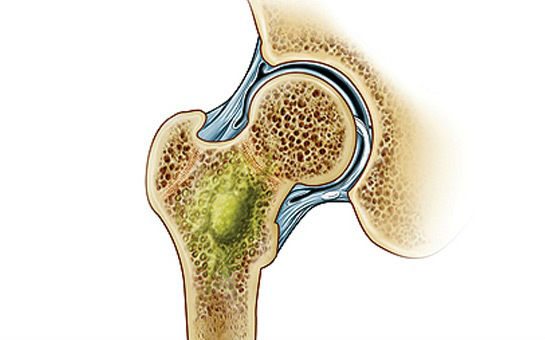

Инфекционные агенты, проникая из внешней среды или хронического очага внутри организма, способны поражать любые ткани. В костях формируются гнойные расплавления с образованием секвестров – новых измененных фрагментов, обусловленных работой остеокластов. Эти клетки пытаются противостоять микробной агрессии, восстанавливая костные структуры. Однако эффект их деятельности недостаточен, так как на фоне сниженного иммунитета и высокой инвазирующей способности бактериальных возбудителей гнойное расплавление продолжается. Так формируется остеомиелит – очаг инфекционного поражения костной ткани.

Гнойный очаг.

На фоне ослабления защиты организма бактерии проникают и размножаются в костной ткани. В результате появляется очаг гнойного расплавления.